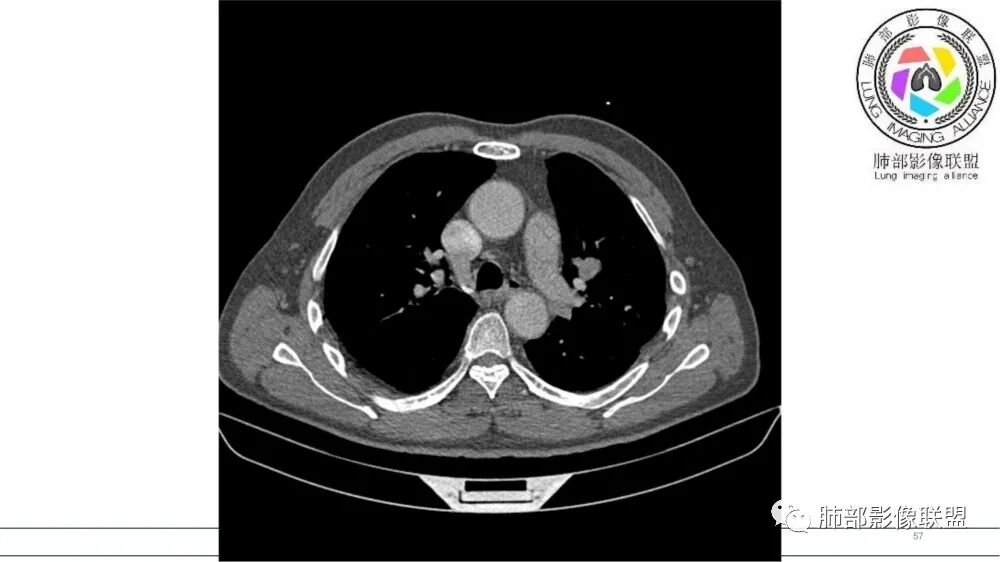

左肺上叶前段支气管杵状指样扩张,内见实性组织阻塞性,并强化明显,边缘饱满,周边多发小斑点影,小花小草征,老年男性,长期吸烟史,方向恶性,首选支气管内浸润鳞Ca可能性大。

B3指套征,常规不是鳞癌就是ABPA,有强化丶血管造影征,倾向于鳞癌

指套征,扩张支气管内软组织强化,远侧肺野阻塞性炎,纵隔、左肺门肿大淋巴结;老年男性,吸烟,考虑鳞癌,鉴别小

2021年8月6日晨读病例结果:小细胞肺癌

指套征:是影像征象,胸部平片表现为手指状密度增高影,以肺门为中心呈放射状分布,CT显示扩张支气管内低密度黏液栓形成或实性病变,呈管状、树枝状或卵圆形密度增高影;支气管扩张伴近端梗阻时,扩张支气管内部黏液分泌物不能排出而形成。可以伴随远端空气潴留征、阻塞性炎症。

研究报道,中心型 SCLC 经 CT 扫描后通常支气管表现为鼠尾样狭窄,肺门或纵隔肿块明显,由于肿块沿管壁生长表现为顺延支气管形态的不规则形状。病灶相对特征性影像学表现比如鸭蹼状、腊肠状、葫芦状及葡萄状改变,可以出现血管包埋,很少有空洞、空泡,较少引发肺不张,阻塞性炎症成都较轻。与一般肺癌比较,恶性程度高,侵袭力强、病灶很小就容易远处转移!Herzberg 等[19]研究指出,20%以上 SCLC 倍增时间短,预后不良。